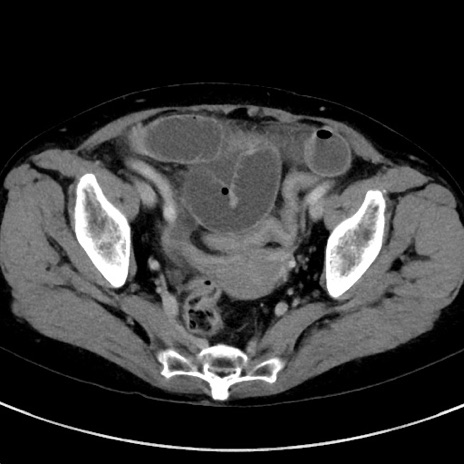

症例23(横断像)

【症例】70歳代女性

【主訴】下腹部痛・嘔吐

【現病歴】2日前より腹痛あり。昨日嘔吐あり。症状改善しないため来院。

【既往歴】胃GISTに対して胃部分切除後。

【身体所見】BT 37.1℃、BP 128/77mmHg、腹部:平坦・軟、下腹部に圧痛あり。

【データ】WBC 10200、CRP 0.31